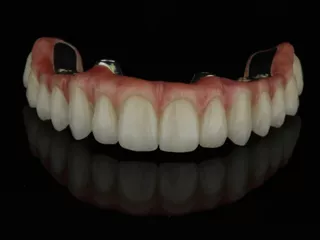

18a. 18b. Images of the upper restoration.

18a

18b

19a. 19b. Images of the lower restoration.

19a

19b